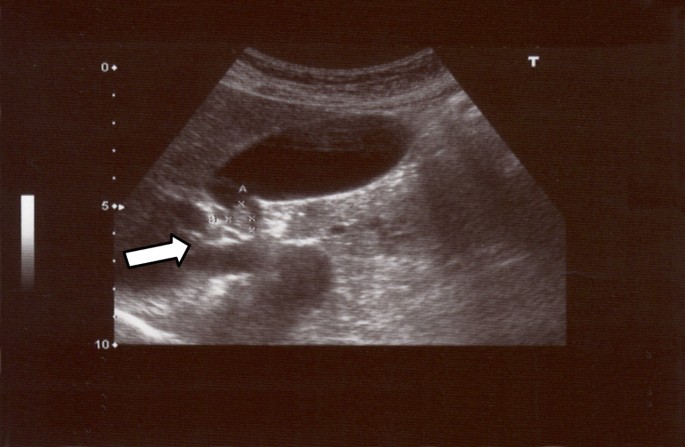

Анатомия и особенности Гартманова кармана желчного пузыря